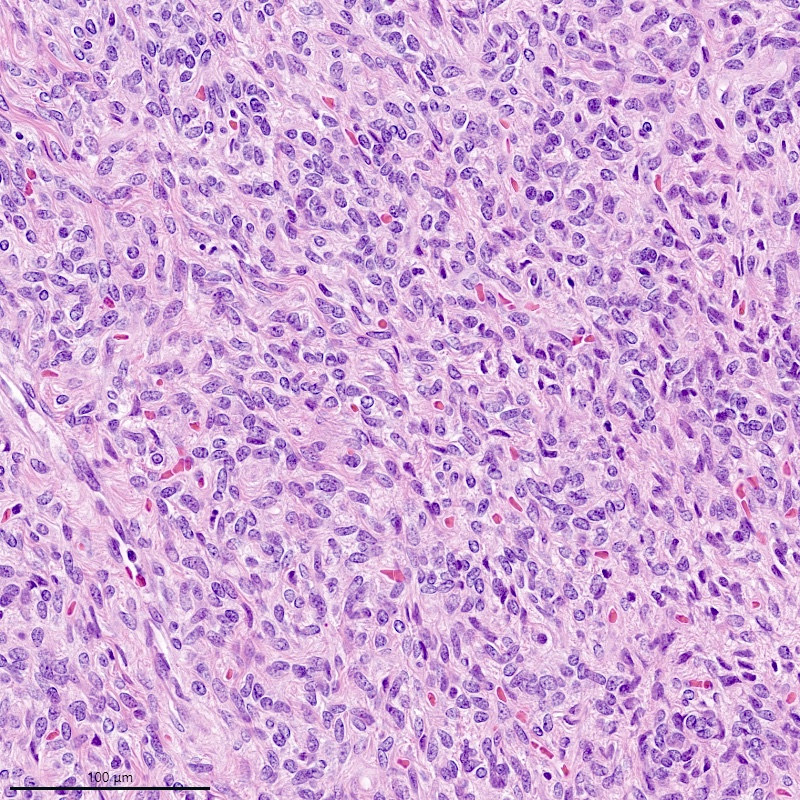

Microscopic (histologic) description

- Irregular cellular islands, forming permeative tongue-like pattern of myometrial invasion with frequent vascular invasion

- Monotonous oval to spindle cells with minimal cytologic atypia, vesicular chromatin and scant cytoplasm

- Mitotic count is usually low (< 5/10 high power fields), necrosis is usually absent

- Tumor cells may whorl around delicate arteriolar type vessels, reminiscent of proliferative phase endometrial stroma

- May have admixed collagen bands / plaques and foamy histiocytes

- May have smooth muscle differentiation, particularly in a starburst morphology, with collagen bands radiating towards the periphery of the nodule

- Other reported types of differentiation: fibromyxoid / fibrous, sex cord-like, epithelioid, rhabdoid, endometrioid glands, pseudopapillae, clear cells, bizarre cells, adipose tissue (Mod Pathol 2016;29:S92)

Microscopic (histologic) images

Contributed by Elizabeth Kertowidjojo, M.D., Ph.D., M.P.H. and Ayse Ayhan, M.D., Ph.D.